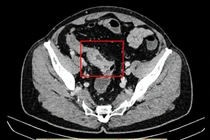

Kết quả chụp X-quang, siêu âm và cắt lớp cho thấy dạ dày chứa nhiều chất đặc quánh, hình ảnh bã thức ăn gây tắc ruột. Người bệnh được chẩn đoán tắc ruột do bã thức ăn, chỉ định phẫu thuật mở dạ dày lấy khối bã. Sau mổ, bác sĩ ghi nhận khối bã lớn, cứng, màu nâu đen, nguyên nhân gây tắc nghẽn kéo dài dẫn đến nhiễm trùng, suy thận cấp và suy đa tạng.